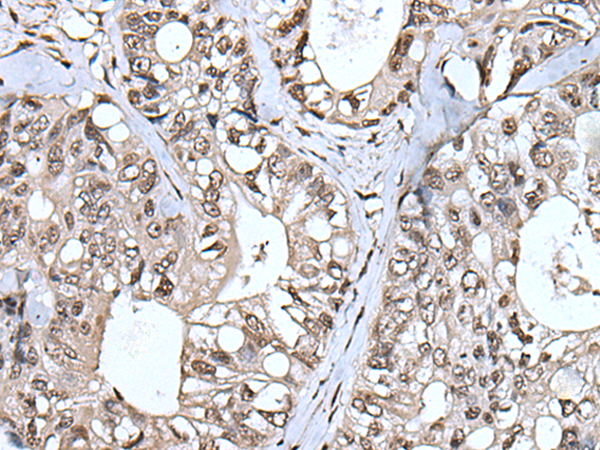

IHC positive control:

Human colorectal cancer and human tonsil

IHC Recommend dilution:

40-250